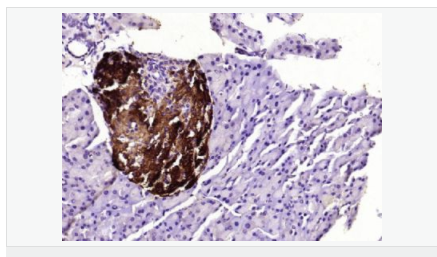

| 產(chǎn)品應(yīng)用 | WB=1:500-2000 ELISA=1:5000-10000 IHC-P=1:100-500 IHC-F=1:100-500 ICC=1:100-500 IF=1:100-500 (石蠟切片需做抗原修復(fù)) not yet tested in other applications. optimal dilutions/concentrations should be determined by the end user. |